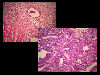

Histology

Histopathological Classifications

Malignant epithelial tumor/Adenocarcinoma